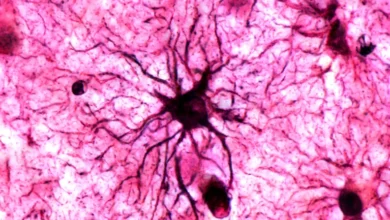

تخریب ارتباطات عصبی علت آلزایمر

پژوهش تازهای نشان میدهد بیماری آلزایمر ممکن است با فعالکردن یک «کلید مولکولی» مشخص، مغز را فریب دهد تا ارتباطات…

درمان آلزایمر نیازمند رویکردهای جدید

به گزارش پایگاه علمی خبری دانه، به نقل از سایت ساینسدیلی (sciencedaily) پژوهشگران دانشگاه متروپولیتن اوساکا در ژاپن، به رهبری…